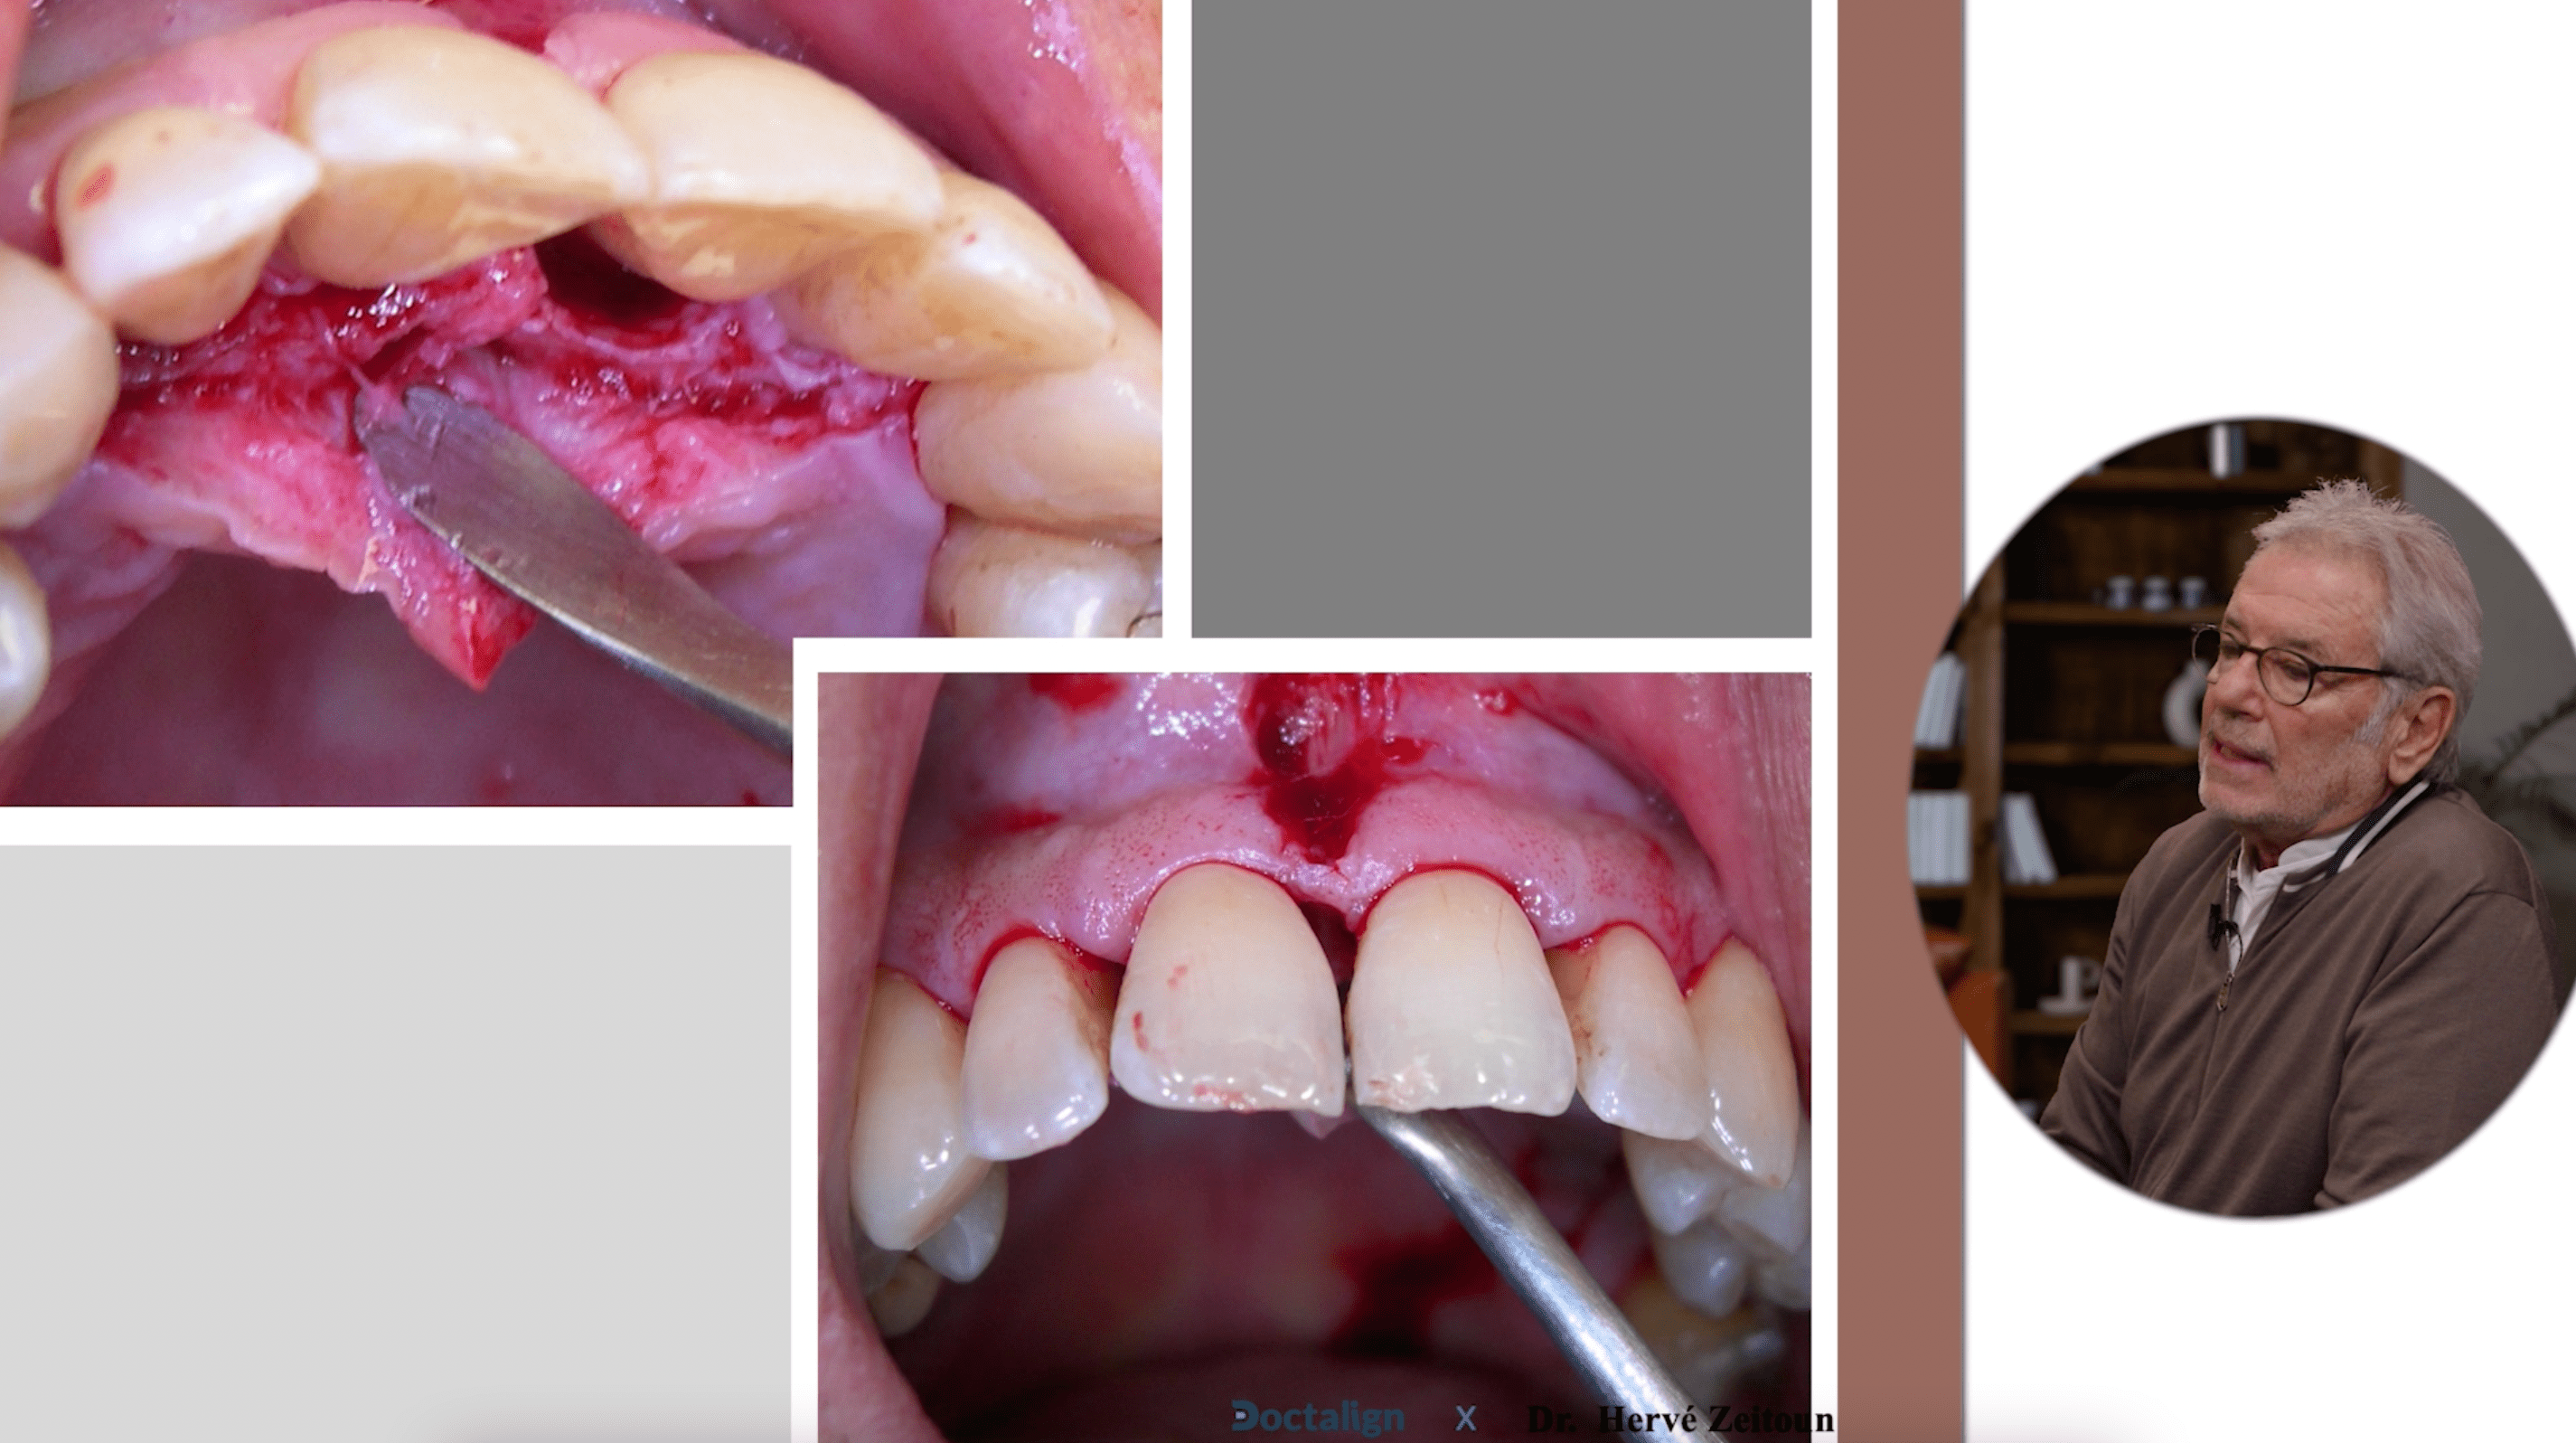

Techniques chirurgicales

Ce chapitre de la formation détaille pas à pas les techniques chirurgicales spécifiques du Dr. Zeitoun pour la frenectomie, offrant des méthodes précises et innovantes qui optimisent l'efficacité du processus, permettant ainsi de gagner un temps précieux lors de l'intervention.